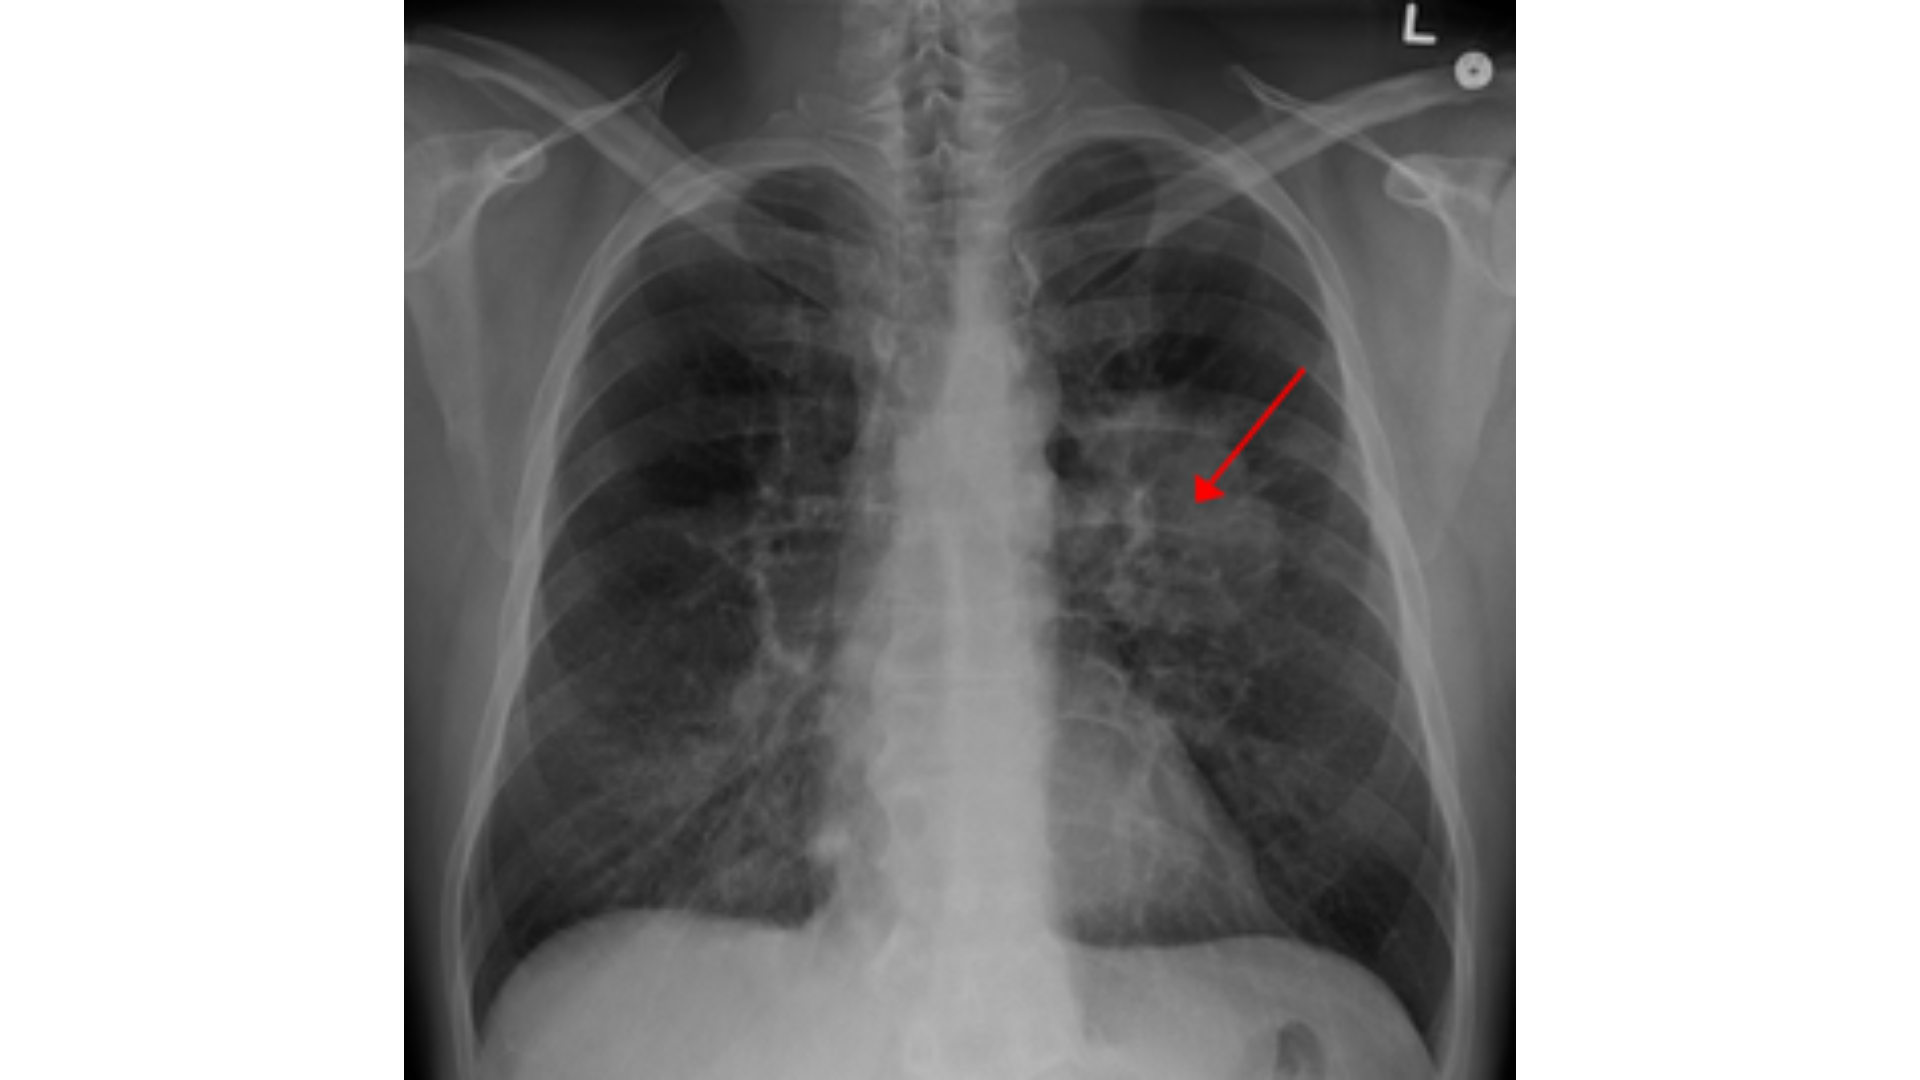

й в легких

Лей в легких 106 фотографий